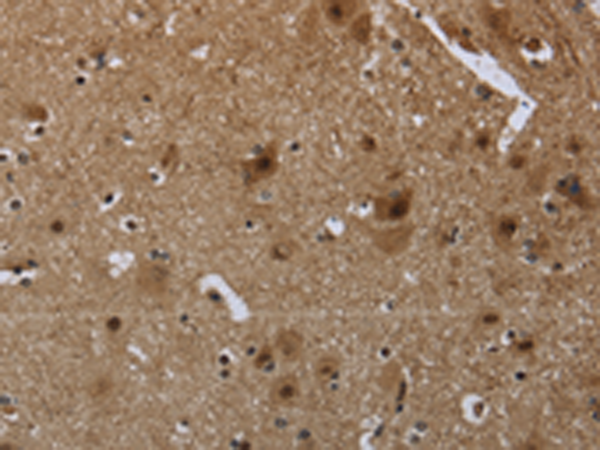

The image is immunohistochemistry of paraffin-embedded Human esophagus cancer tissue using (GYPC Antibody) at dilution 1/60. (Original magnification: ×200)

The image is immunohistochemistry of paraffin-embedded Human brain tissue using (GYPC Antibody) at dilution 1/60. (Original magnification: ×200)